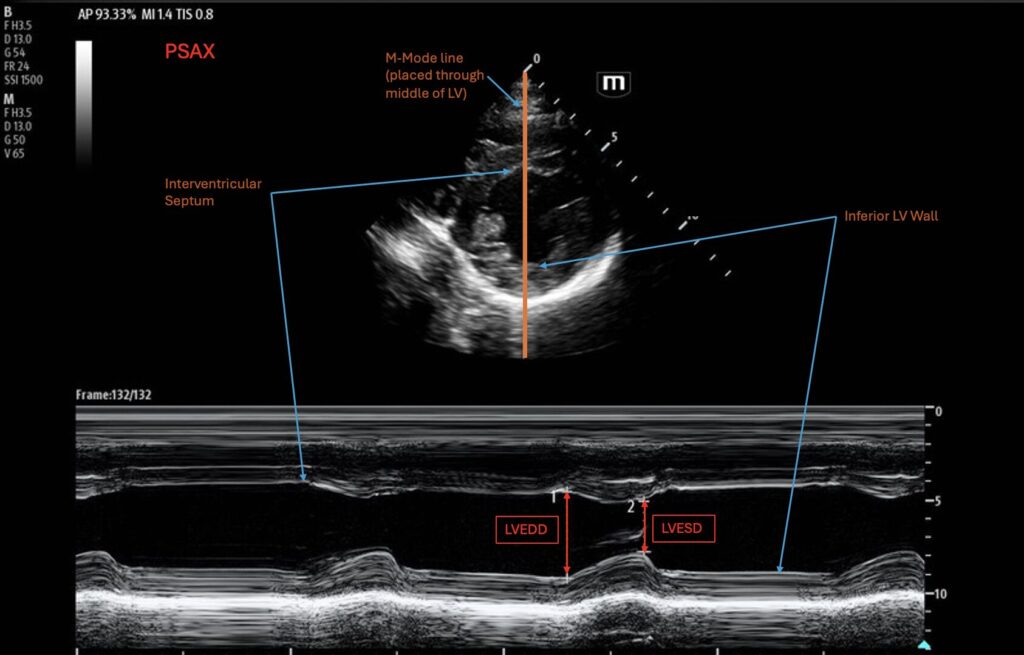

How to do

FS can be measured in the parasternal long axis (PLAX) view or the parasternal short axis (PSAX) at the level of the mid-ventricle (papillary muscles). M-mode is used and placed in the middle of the LV. At this stage, it is important to make sure the M-mode is not capturing the mitral valve or the papillary muscles. On the M-mode tracing, two measurements of LV diameter are taken via the distance between the anterior and posterior walls of the ventricle at end-systole and at end-diastole. These diameter measurements of LVEDD and LVESD are taken, and most modern US machines will calculate the percent fractional shortening based on the equation above. It is important that this measurement should be taken when you are directly perpendicular to the ventricle.

Normal values

Although fractional shortening is calculated as a percent, it is important to note that it is calculating a distance rather than a volume, so the normal ranges do not directly represent EF%, although these measurements can be used to derive an EF% through Teichholz equation18:

Vd = [7/(2.4 + LVEDD)] x LVEDD3

Vs = [7/(2.4 + LVESD)] x LVESD3

LVEF = (Vd – Vs)/ Vd

The normal range for FS is 25-43% for men and 27-45% for women19. A measurement less than 15% corresponds to severely reduced LVEF of less than 30%7,19.